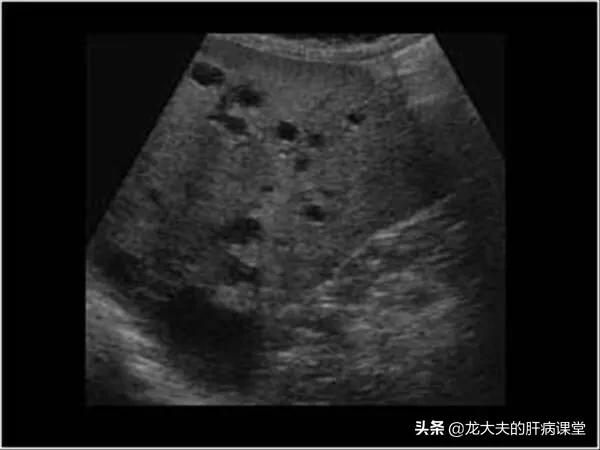

このタイプの肝嚢胞は良性病変であり、通常は明らかな臨床症状がなく、超音波検査やCT検査で偶然発見されるだけである。また、患者に腹痛や腹部不快感を引き起こす一部の大きな嚢胞だけが、通常女性に多い。

多発性肝嚢胞の肝機能の検査は一般的に正常であり、肝臓領域の超音波検査では、1つ以上の液体の安全性を見ることができます。 CTまたは核スキャンはまた、多発性肝嚢胞があるかどうかをチェックすることができ、さらに多発性肝嚢胞は実質的な病変がないことを決定することができます。